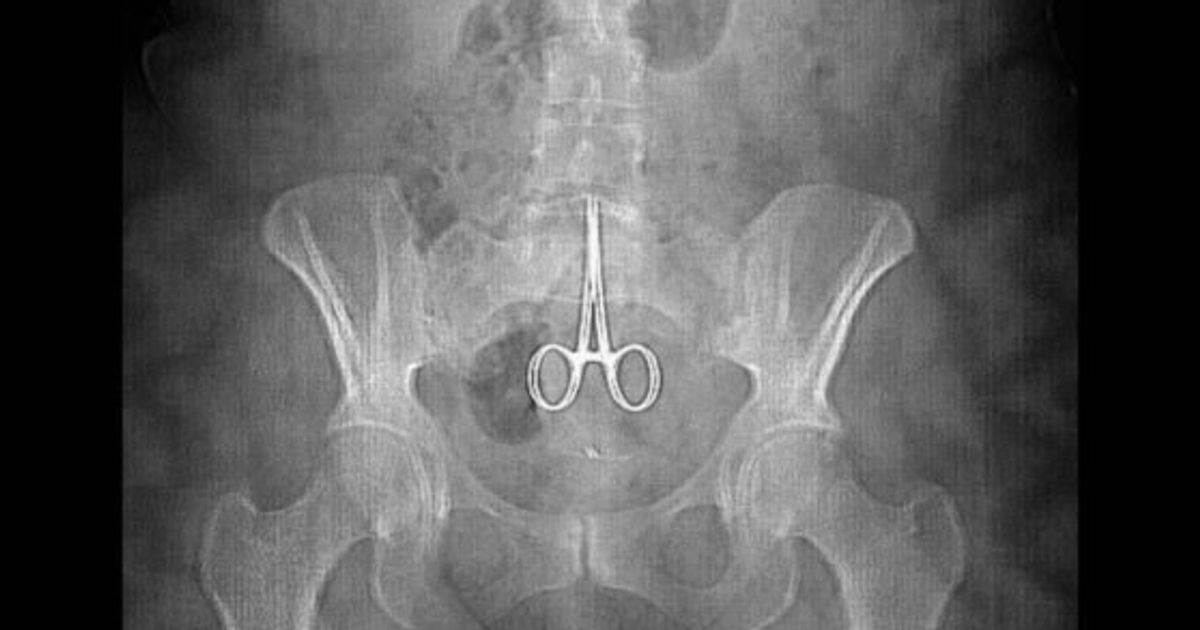

フォーク2本、ボールペン、歯ブラシを飲み込んでしまった患者の腹部レントゲン写真です。これらの異物が腸内に留まっているのが確認できます。なぜ飲み込んでしまったのか、その理由は不明ですが、異常な行動が原因と考えられます。